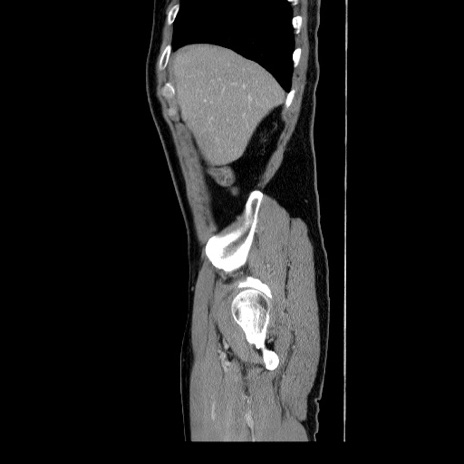

症例34(矢状断像)

【症例】60歳代 男性

【主訴】右鼠径部膨隆

【現病歴】1年程前より右鼠径部膨隆あり。自己にて還納可能だったため放置していた。3時間前より右鼠径部の脱出を認め、還納困難となり受診。

【身体所見】右鼠径部に小児頭大の膨隆あり。弾性硬であり、用手還納は困難。左鼠径部にも膨隆を認める。脱出はなし。